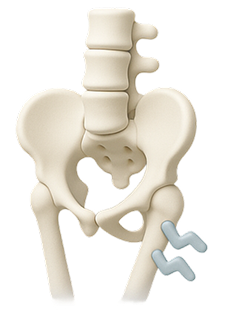

When the soft center of a spinal disc pushes through a crack in the exterior, it can press on nerves and cause pain.

Lower back pain can stem from several underlying issues, including: